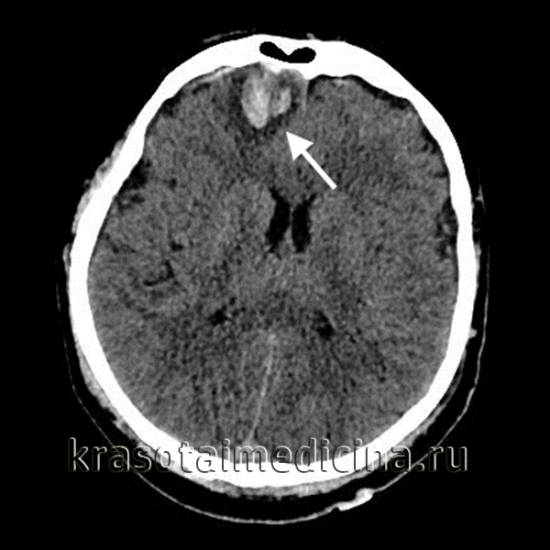

Основным методом диагностики ушиба головного мозга (УГМ) является компьютерная томография (КТ). Томографическая картина варьируется в зависимости от степени тяжести ушиба. При легкой степени очаги с пониженной плотностью выявляются в 40-50% случаев. В зоне ушиба на томограммах наблюдаются отечность и петехиальные кровоизлияния. Отек может охватывать всю долю мозга или целое полушарие, что приводит к умеренному сужению ликворных пространств.

На аксиальной КТ головного мозга без контрастного усиления определяется контузионный очаг в правой лобной доле, состоящий из геморрагического компонента, зоны детрита и отека.

Ушиб средней тяжести характеризуется наличием очагов ушиба на томограммах в виде зон пониженной плотности. При геморрагическом пропитывании очаг может иметь повышенную плотность. При тяжелом ушибе томография показывает как очаги повышенной, так и пониженной плотности. В первом случае это сгустки крови, во втором — участки размозжения и отека. При крайне тяжелых поражениях зона деструкции церебральной ткани проникает в подкорковые структуры.